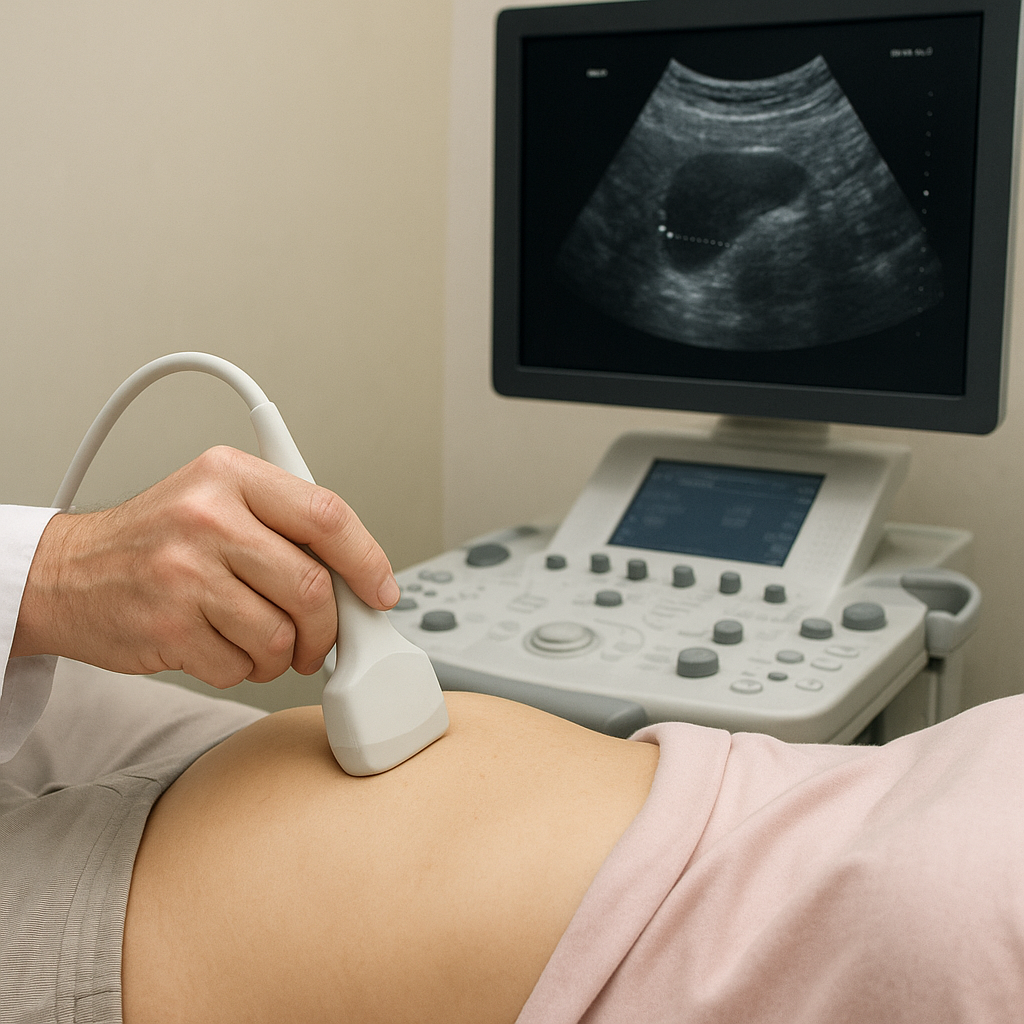

Ultrasonografia, czyli nieinwazyjna metoda o szerokim zastosowaniu w medycynie, bazuje na odbiciu fal dźwiękowych o wysokiej częstotliwości.

Sondę USG przykłada się do skóry górnego odcinka jamy brzusznej, co pozwala w czasie rzeczywistym śledzić kształt, rozmiar i strukturę pęcherzyka żółciowego. W odróżnieniu od innych badań obrazowych, ultrasonografia nie wykorzystuje promieniowania jonizującego, co czyni ją bezpieczną nawet dla kobiet w ciąży czy osób przewlekle leczonych.

Dzięki technologii Dopplera możliwa jest również ocena przepływu krwi w naczyniach otaczających pęcherzyk, co bywa pomocne przy podejrzeniu zmian zapalnych czy rozrostowych. W doświadczonych rękach badanie USG staje się narzędziem o dużej czułości i swoistości w wykrywaniu patologii pęcherzyka żółciowego.